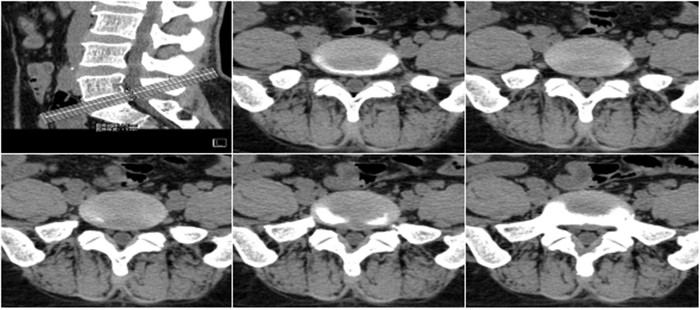

明峰CT搭載了領(lǐng)先的硬件技術(shù)平臺及系統(tǒng),強(qiáng)大的掃描能力可滿足臨床的各種要求,呈現(xiàn)更極致的細(xì)節(jié),為各臨床科室提供高品質(zhì)的圖像。薄層掃描,消除部分容積效應(yīng),提高各向同性。配合高分辨率算法,有助于細(xì)微結(jié)構(gòu)和形態(tài)學(xué)顯示。